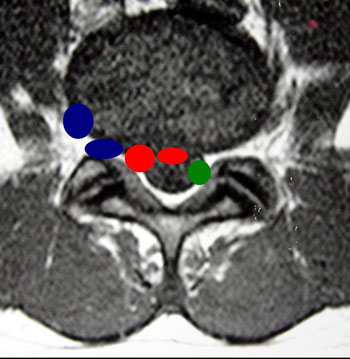

Em relação à localização ela pode ser central, centro lateral, foraminal e extra-foraminal (Fig 1).

Fig. 1

A zona triangular de segurança foi inicialmente descrita por Mirkovic . em 1995, que a definiu como um espaço da zona foraminal, em formato triangular, onde poder-se-ia introduzir com segurança, cânula de procedimento em procedimentos percutâneos póstero-laterais lombares sem colocar em risco as estruturas vásculo neurais circunjacentes. É o local onde são efetuados os procedimentos percutâneos póstero-laterais lombares.

Choi em 2000 realizou um estudo de dissecção anatômica em quatorze cadáveres humanos frescos, num total de 100 zonas foraminais estudadas, e concluiu que a zona triangular de segurança apresenta tem como limites: lateral – o nervo, inferior – platô vertebral superior da vértebra inferior e medial – a dura-máter espinal; e ainda que a mesma admite cânula de procedimento de diâmetro externo progressivamente maior de L2-L3 a L5-S1 e a menor média encontrada ao nível L2-L3 foi de 7,55 mm e a maior ao nível L5-S1 foi de 12,59 mm, portanto bem acima da maior cânula que é utilizada atualmente que é 6,4 mm.